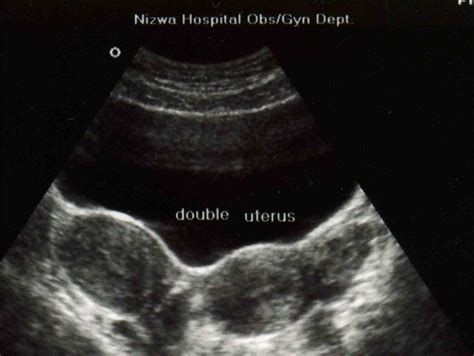

When individuals search for Didelphic Uterus Pictures, they are often seeking clarity on how their anatomy differs from the standard uterine structure. Medical imagery, such as MRIs, ultrasounds, and 3D pelvic reconstructions, provides the best visual representation of this double structure. Unlike a bicornuate uterus—where the two horns are connected—the Didelphic uterus consists of two completely independent units.

Viewing these medical images helps patients understand why they may experience certain symptoms. For example, the presence of two cervices is a hallmark feature visible in clinical scans. Understanding these visuals can help patients communicate more effectively with their gynecologists during consultations.

| Transvaginal Ultrasound | Initial screening to visualize the uterine structure. |